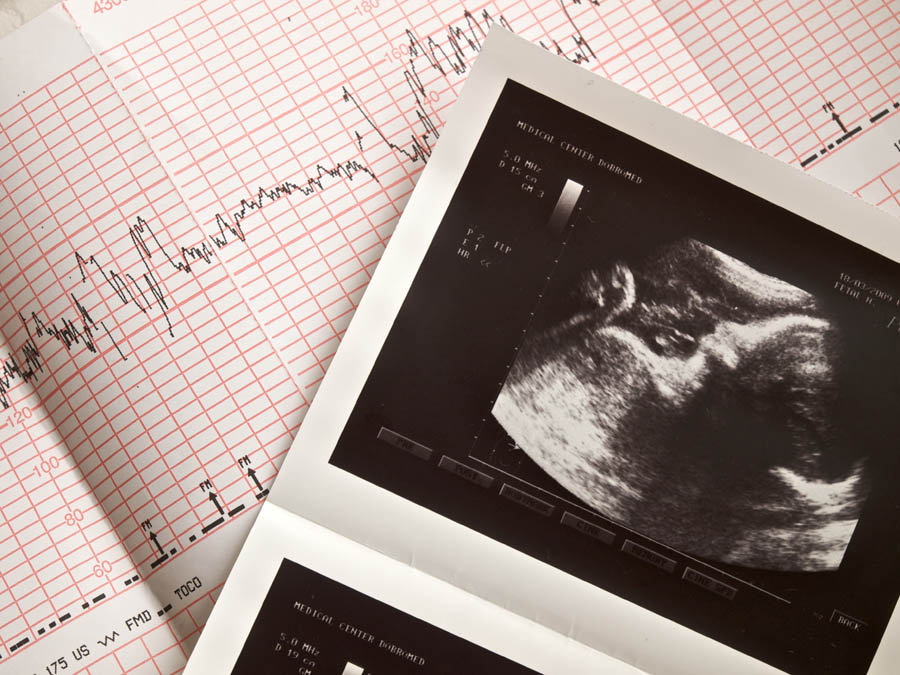

In March 2020, the British government put in place a temporary approval in England, enabling women to have early medical abortion (EMA) at home.

Just following a telephone or e-consultation with a clinician, women can take the two sets of pills for EMA within the first 10 weeks of gestation in their own homes. The first medication prevents continued development of the embryo and the second forces the expulsion of the embryo from the uterus.

Prior to the pandemic, only the second pill for EMA could be taken at home; the first set had to be administered by a doctor after an in-person consultation, to assess the woman or girl’s mental and physical health prior to the abortion.

EMA accounts for the vast majority of abortions that occur in England and Wales, and accounted for 73% of abortions in 2019.